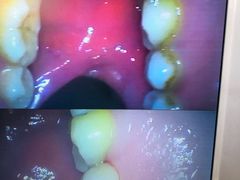

• -新达口腔(华东理工大学店)

zxqvini77 | 21-04-23